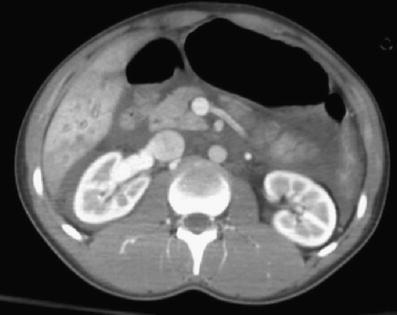

Fig. 1

Chest CT image at the level of the ventricles shows pericardial effusion and interventricular septum bowing